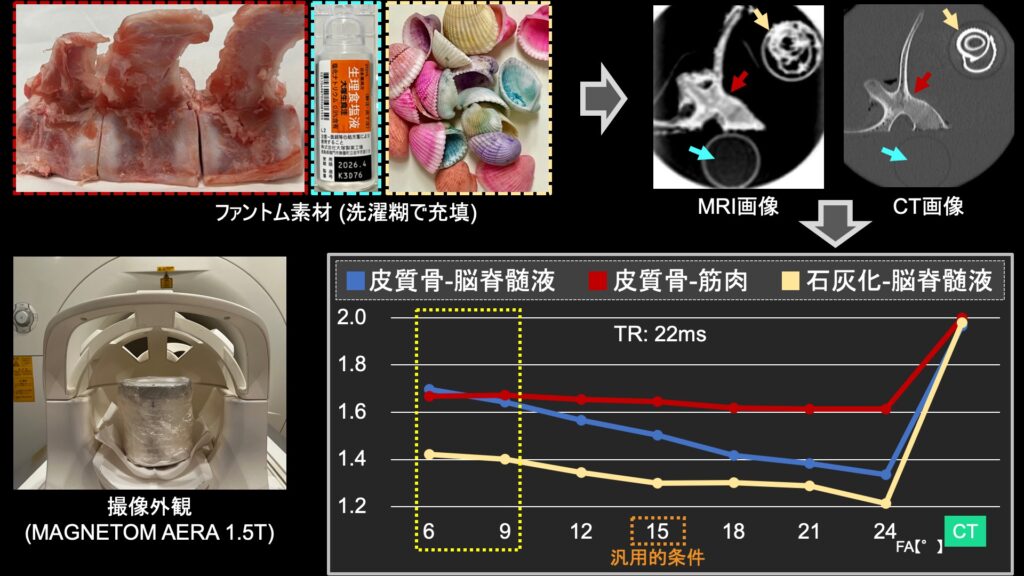

肝の最新MRI 伸弘, 谷本

金原出版

2004/5/1